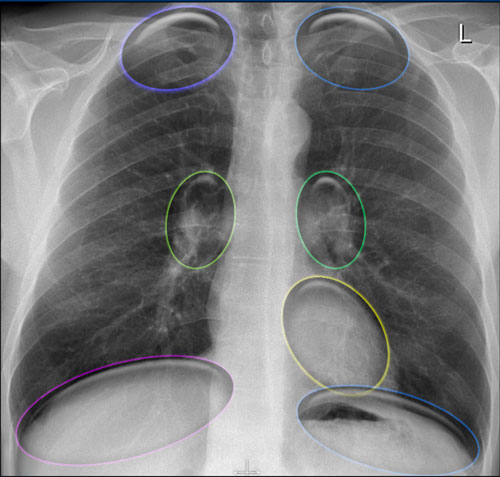

Hidden Areas on Chest Radiography

Certain regions of the chest are prone to being overlooked on standard chest radiographs due to overlapping anatomical structures. These are referred to as the "hidden areas", and they warrant particular attention during image interpretation to avoid missing subtle or significant pathology.

Key Hidden Areas:

• Apical zones

• Hilar regions

• Retrocardiac region

• Subdiaphragmatic zone (below the diaphragmatic domes)

Hidden Areas (1)

It’s important to recognize that a substantial volume of lung parenchyma extends below the dome of the diaphragm, particularly in the posterior lower lobes.

This area (illustrated in blue) must be carefully evaluated.